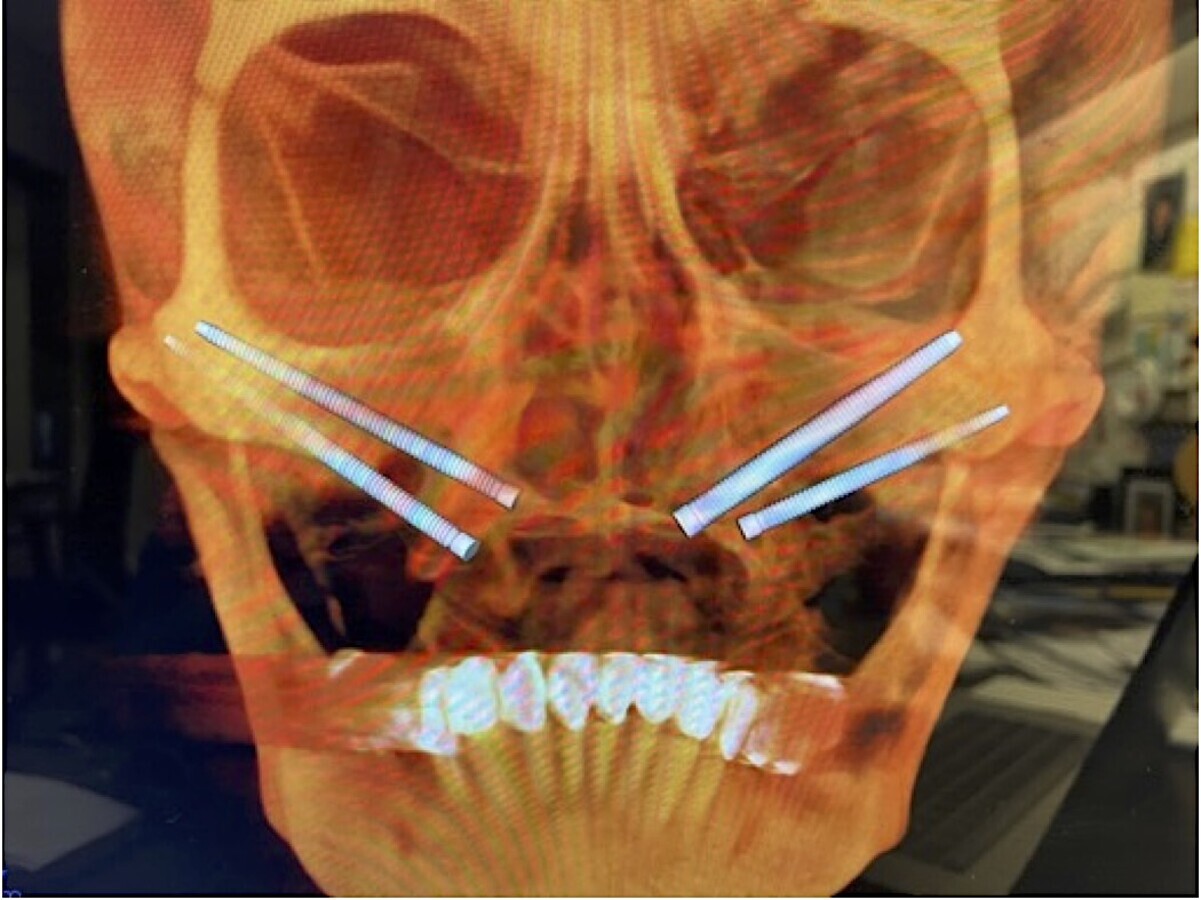

Fig. 2. Planeamiento tridimensional de la colocación de los 4 implantes zigomáticos.

Fig. 8. Imagen topográfica postoperatoria inmediata de Quad Zygoma.